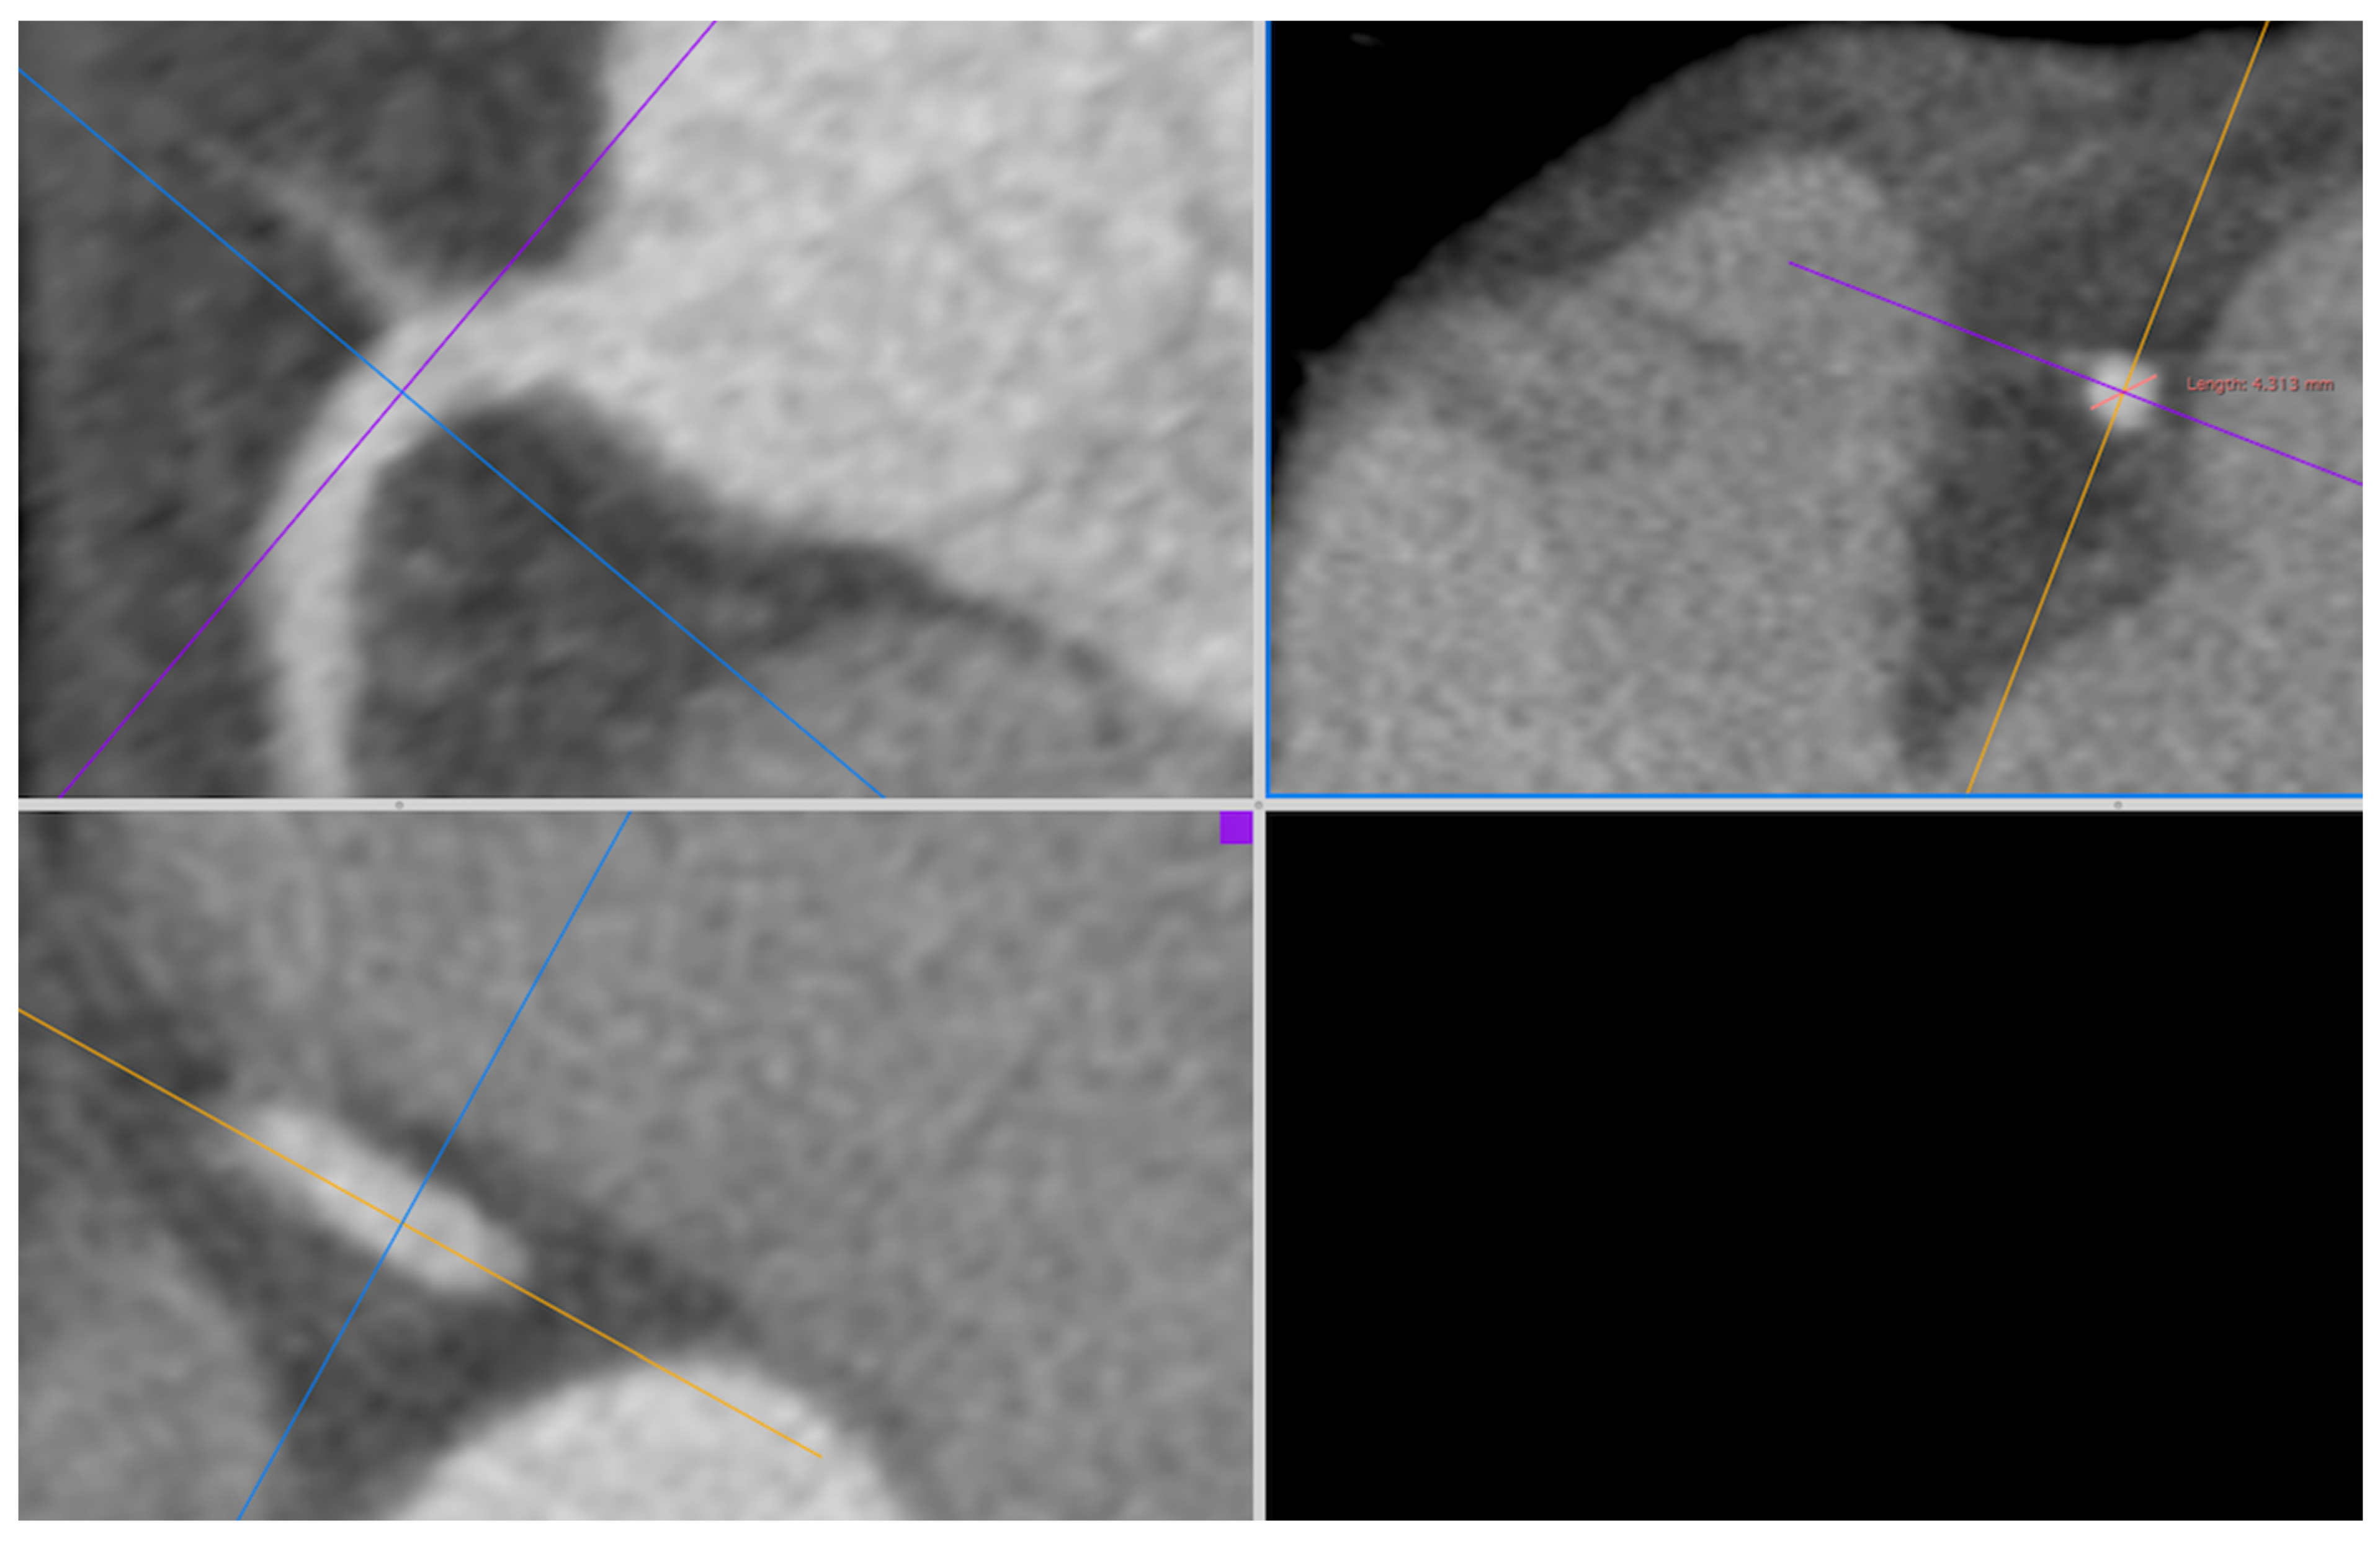

The CT examinations were analyzed by a radiologist with 10 years of experience in cardiac imaging. All assessments were executed using Horus software version 3.3.6. The measurement of coronary artery diameters, ascending aortic diameter (AscAoD), and main pulmonary artery diameter (MPAD) was conducted on three-dimensional curved multiplanar reformatted images. The measurement of coronary artery diameters and AscAoD was conducted from oblique axial planes that were perpendicular to the vessel axis on coronal and sagittal images. The luminal diameter of the LM was measured from the midsection, and the luminal diameters of the left anterior descending artery (LAD), left circumflex artery (LCX), and right coronary artery (RCA) were measured within 1 cm of the origin of each artery (Figure 1). The AscAoD measurement was taken at a point approximately 4 cm above the aortic annulus. The MPAD measurement was taken from the widest part before the bifurcation, where it was perpendicular to the vessel wall. The measurement of left atrial area (LAA) and right atrial (RA) area (RAA) was performed on four-chamber views by tracing the inner borders of the chambers at the end-systolic phase on the slices where the chambers appeared the largest. The measurement of LV diastolic diameter (LVDD) and right ventricular (RV) diastolic diameter (RVDD) was performed on four-chamber views from the midseptum to the lateral wall at the end-diastolic phase on the slices where the chambers appeared the largest. The septal thickness (ST) was measured in the midseptum on end-diastolic short-axis views, and the posterior wall thickness (PWT) was measured from the basal inferior wall on end-diastolic short-axis views. The LV mass index (LVMi) was calculated by indexing the LV mass estimated by Devereux’s formula to BSA [15].

Figure 1. Three-dimensional curved MPR CT image depicting the measurement of RCA diameter; CT: computed tomography; MPR: multiplanar reformatted; RCA: right coronary artery.